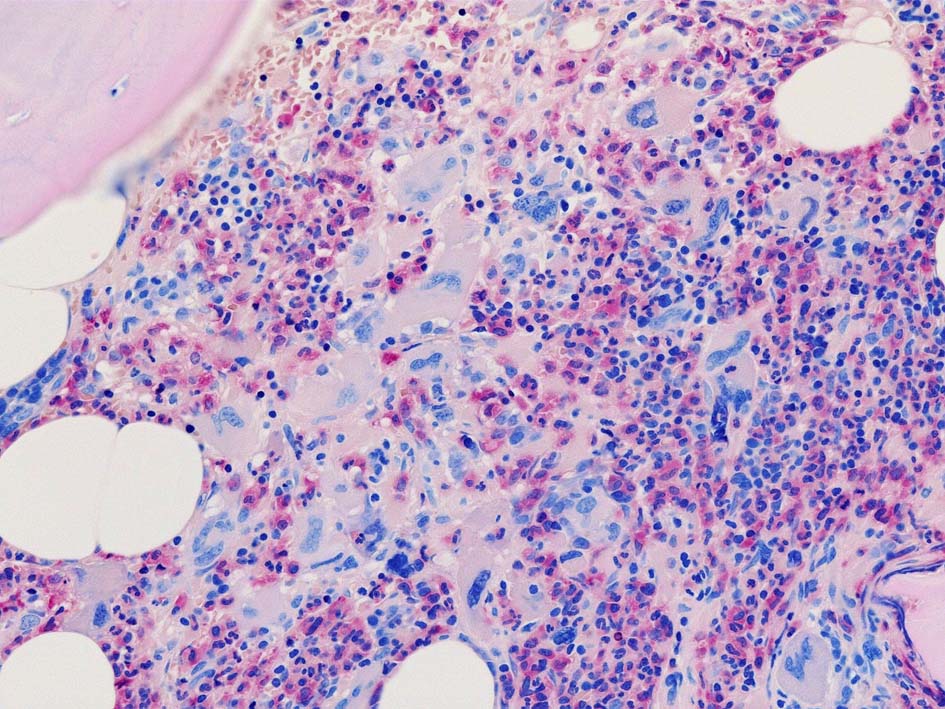

黒染する弾性線維の増生のほか, 赤く染まる膠原線維の増生が確認される. MF-2 fibrosis. 鍍銀染色の核染色をすると膠原線維の赤染がわからなくなるので行わない.